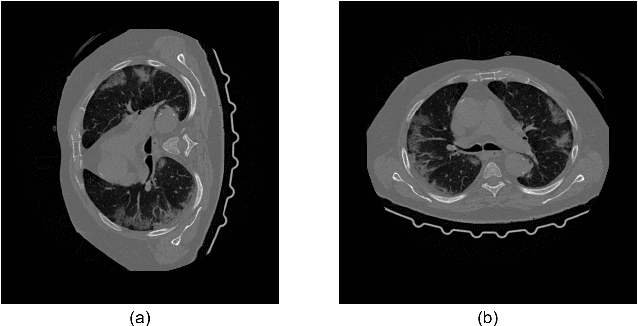

Abstract:We present a deep-learning based computing framework for fast-and-accurate CT (DL-FACT) testing of COVID-19. Our CT-based DL framework was developed to improve the testing speed and accuracy of COVID-19 (plus its variants) via a DL-based approach for CT image enhancement and classification. The image enhancement network is adapted from DDnet, short for DenseNet and Deconvolution based network. To demonstrate its speed and accuracy, we evaluated DL-FACT across several sources of COVID-19 CT images. Our results show that DL-FACT can significantly shorten the turnaround time from days to minutes and improve the COVID-19 testing accuracy up to 91%. DL-FACT could be used as a software tool for medical professionals in diagnosing and monitoring COVID-19.